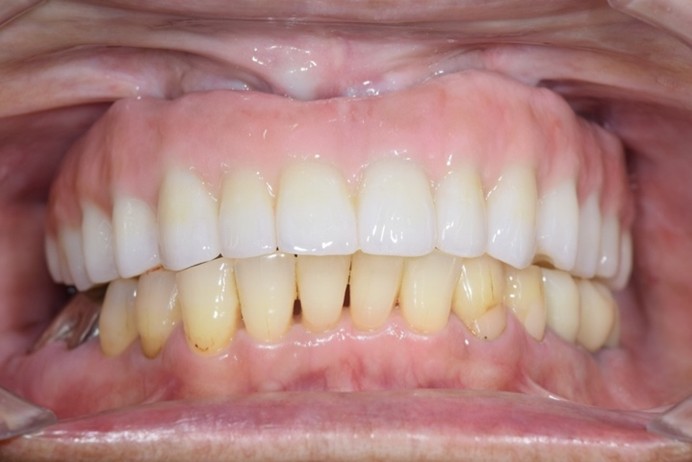

症例1

| 術前 | 術後 |

| ご来院時の主訴 | 入れ歯を入れたが落ちてくる。 インプラントの話を聞いたので入れ歯じゃなくてインプラントをしたい。 |

| 年代・性別 | 70代 女性 |

| 治療部位 | 上顎7〜7 |

| 治療費用 | 2,420,000円 |

| 手術回数 | 2回 |

| 治療期間 | 25か月 |

| 手術時間 | 90分×2回 |

| 治療回数 | 28回 |